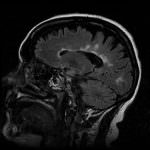

La sclerosi multipla colpisce la la guaina di mielina che protegge i nervi. Ad oggi, la scienza, nella nube di fattori genetici ed ambientali, propone due possibili cause.